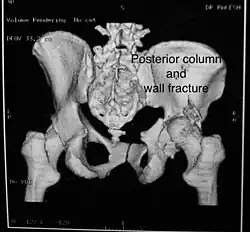

Posterior column and wall fracture as seen on 3D CT

Posterior column and wall fracture as seen on 3D CT -

Posterior column and wall fixed using screws and plates

Posterior column and wall fixed using screws and plates

| Posterior column | As with posterior wall injury, this also typically occurs due to dash board injury. | Posterior column + Posterior wall | These fractures are extensions of elementary fractures. With the involvement of the posterior wall, the difficulty in treatment increases. These fractures are rarely amenable to non-surgical treatment. Due to posterior wall fracture, the hip is usually dislocated posteriorly, requiring immediate reduction of dislocation and surgical reconstruction after a few days.

The posterior column with posterior wall fracture occurs due to dashboard injury. The anteroposterior view may give clues to these injuries. Judet views and CT scans help in knowing the extent of the injury. |